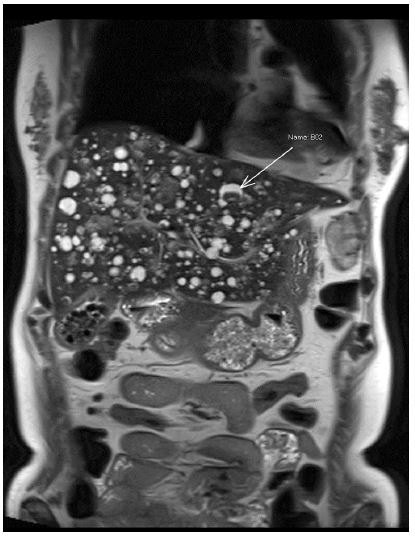

Magnetic resonance imaging of the liver was ordered for further delineation of lesions which revealed multiple liver cystic lesions, some with T1w hyperintense signal while others demonstrated internal filling defects (Figure 1). Differentials included polycystic liver disease or biliary hamartomas. Enhancing splenic lesions were also noted and differentials included hamartoma, lymphangioma, extramedullary haematopoiesis or angiosarcoma.

On an MR liver, the splenic lesions demonstrated heterogenous T1 hypointensity with and T2 hyperintense signal. The liver lesions were found to be cystic in nature, some with internal T1 hyperintense signal and in keeping with foci of haemorrhage. A PET CT demonstrated increased avidity of the splenic, liver and bone lesions.

Figure 3: Coronal T2 weighted image demonstrating multiple cystic liver lesions with internal hypointense components (white arrow).